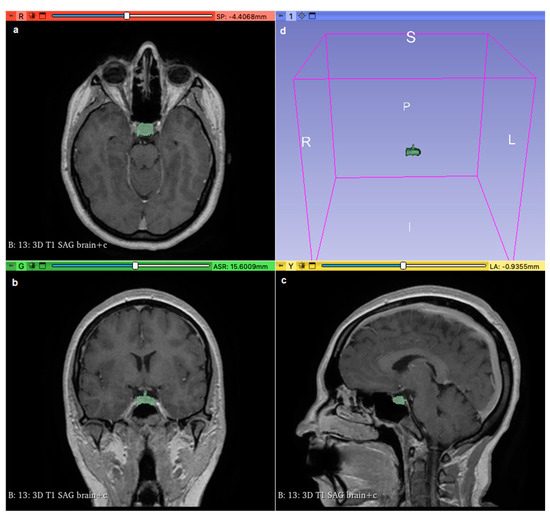

2.5. Volume Measurement

Using Three-Dimensional Slicer software (version 5.0.2 r30822/a4420c3), we analyzed contrast-enhanced weighted-T1 sequences from each participant’s MRI to measure the volumes of the pituitary gland and the pons. Under the supervision of a certified radiologist to ensure accuracy, we manually delineated the borders of the pituitary gland using the ‘Segment Editor’ tool, covering its entire surface area (Figure 1). This delineation was performed across all imaging planes (sagittal, coronal, and axial), and the ‘Grow from seeds’ functionality was employed to refine and smooth the selection. Subsequently, ‘Segment Statistics’ provided measurements of pituitary gland volume in cubic millimeters, including voxel counts. The same procedure was applied to delineate and measure the volume of the pons. To facilitate comparative analysis, we calculated the normalized volume of the pituitary gland by dividing its volume by that of the pons.

Figure 1. Using 3D Slicer software (version 5.0.2 r30822/a4420c3), the pituitary gland (shown in green area) was delineated and covered all its surface areas on axial (a), coronal (b), and sagittal (c) sections; (d) shows the pituitary gland in a 3D view.